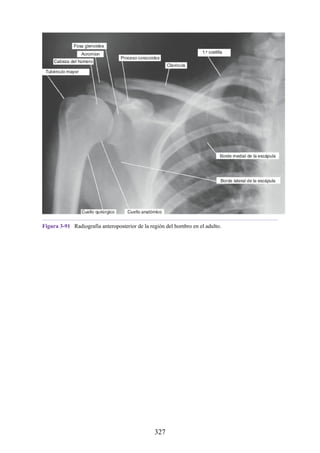

inervación parasimpática.

ACTIVIDAD Más generalizada e indirecta; la